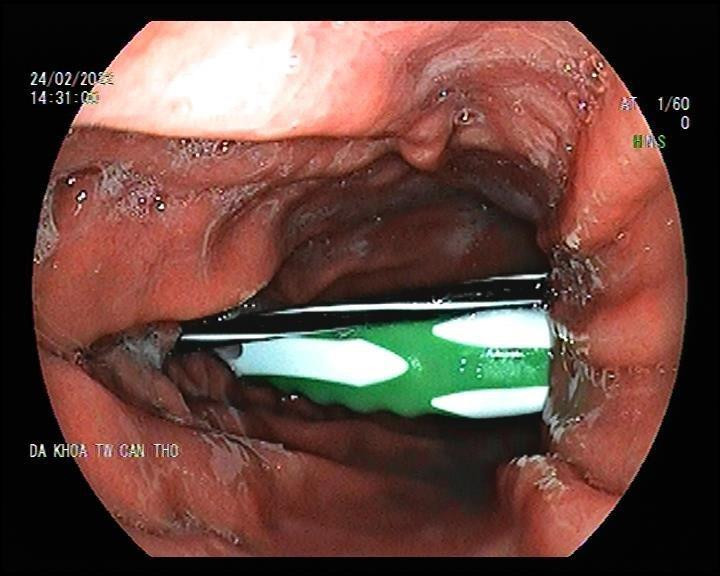

| Các bác sĩ tiến hành nội soi cho P. |

Tiếp nhận bệnh nhân, các bác sĩ tiến hành nội soi dạ dày, tá tràng. Kết quả phát hiện cách cung răng khoảng 38cm ruột bút bi dài khoảng 12cm và 1 thân bàn chải đánh răng dài khoảng 15cm, đường kính 1.5cm, đầu thân bàn chải cắm vào thành tá tràng của P.

Ngay lập tức, ekip đã nhanh chóng tiến hành lấy dị vật qua nội soi, đầu nhọn của dị vật gây ra vài ổ loét 10 - 15mm đáy giả mạc trắng, loét hành tá tràng.